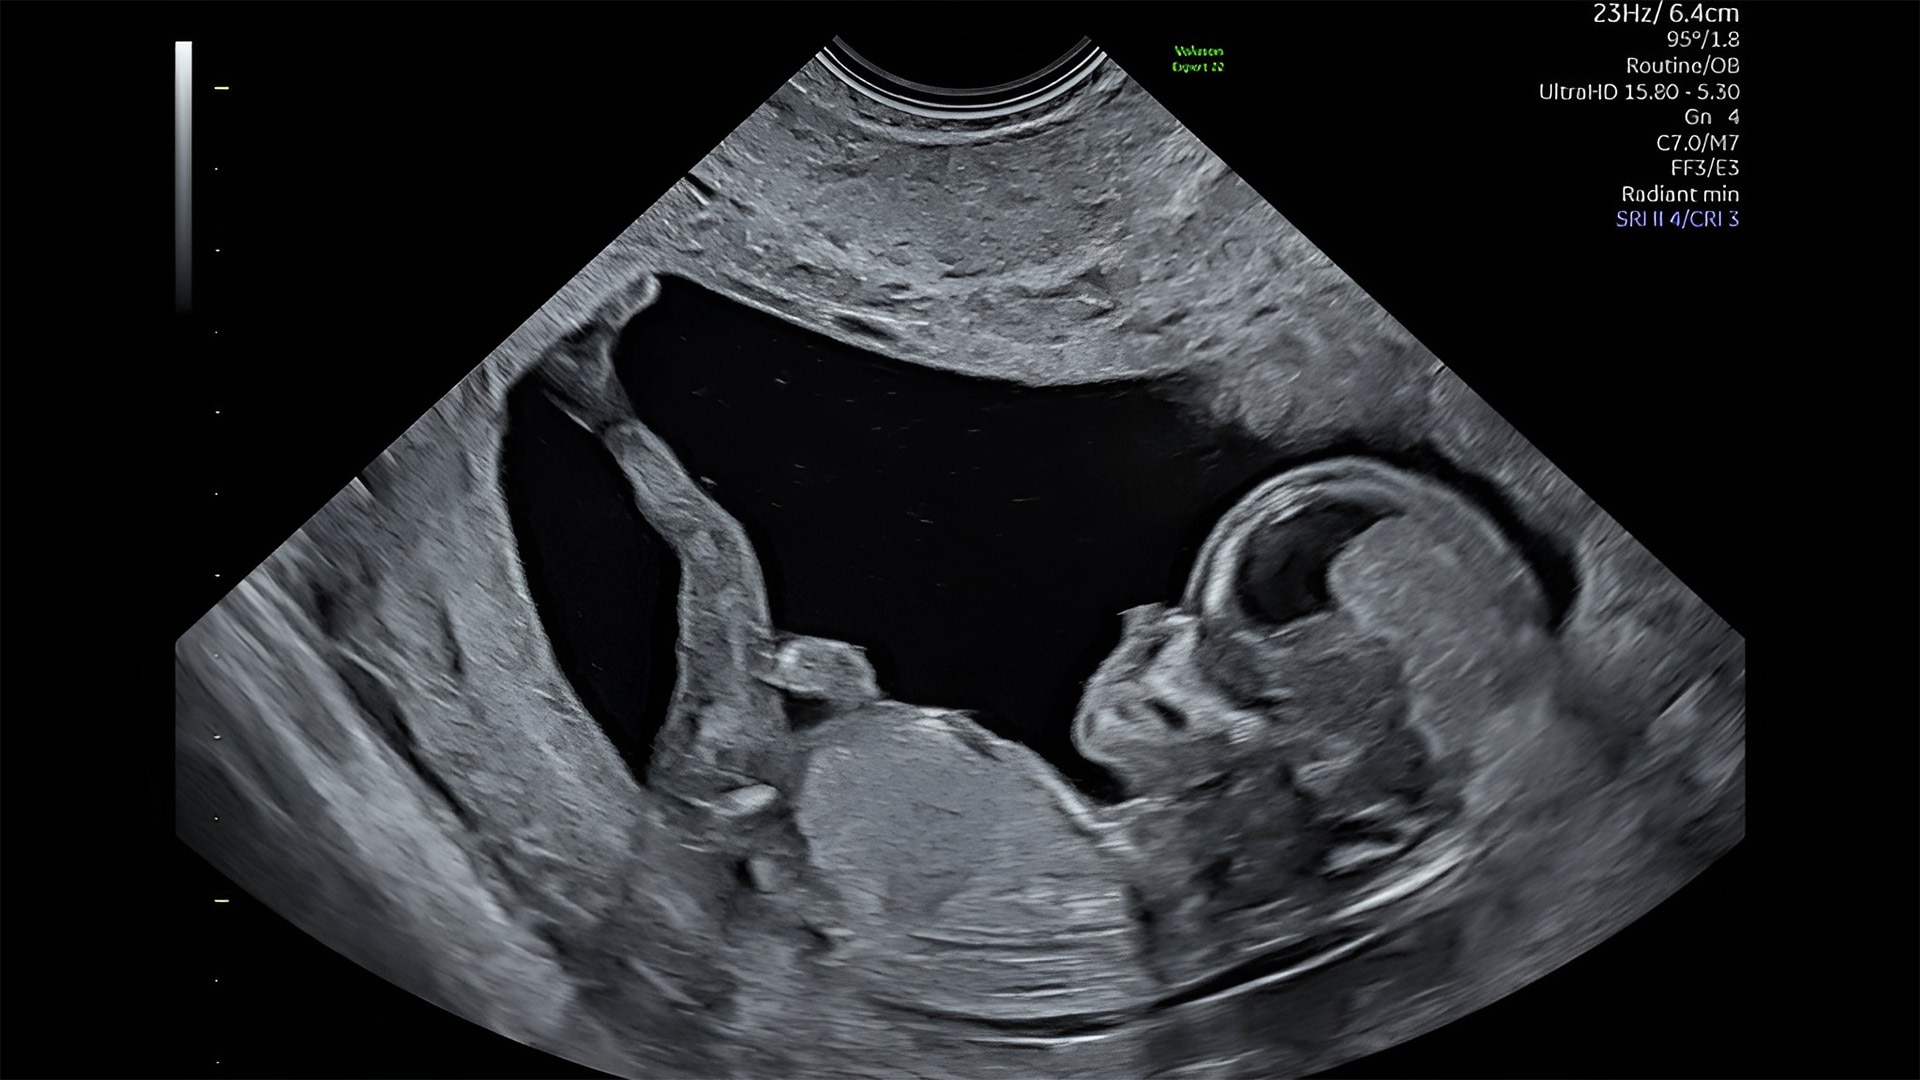

Discover complicated anomalies and pathologies with the Voluson Expert 22 to provide answers sooner for better decision making.

Complex cases come with enough uncertainty. That's why the Voluson Expert 22 is specifically designed for in-depth assessment of complicated anatomy — with pioneering first trimester, fetal cardiac, gynecological, and other pivotal technologies that focus on early detection and intervention.

Identifying fetal cardiac abnormalities earlier means you can intervene sooner, plan for delivery, and potentially improve outcomes. The Voluson Expert 22 provides a full solution of progressive tools, to help distinguish the tiniest structures with stunning clarity to provide patient answers faster.